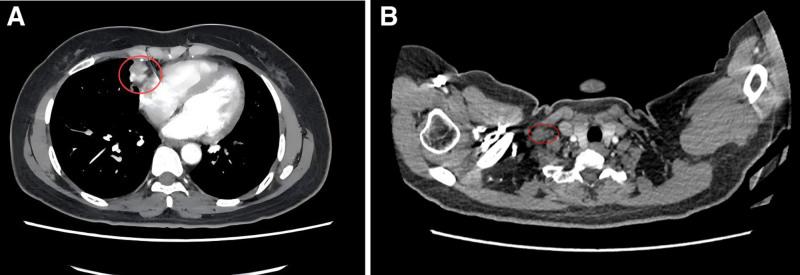

The patient initially received first-line treatment with pembrolizumab combined with docetaxel and nedaplatin, achieving partial response. After progression, second-line therapy included gemcitabine and cisplatin chemotherapy with synchronous radiotherapy, followed by camrelizumab and anlotinib. Regular imaging follow-ups guided therapy adjustments, including extended dosing intervals for camrelizumab during disease stabilization.

Over 4 years of treatment, the patient achieved durable partial response, with significant reduction in tumor burden and no new metastases. As of the most recent follow-up, the patient exhibited an overall survival of 59 months and progression-free survival of 51 months for second-line therapy, with manageable adverse effects including secondary hypothyroidism and grade 2 hypertension.

患者最初接受帕博利珠单抗联合多西他赛和奈达铂的一线治疗,达到部分缓解。进展后,二线治疗包括吉西他滨和顺铂化疗同步放疗,随后是卡瑞利珠单抗和安罗替尼。定期影像学随访指导治疗调整,包括在疾病稳定期间延长卡瑞利珠单抗的给药间隔。

结果